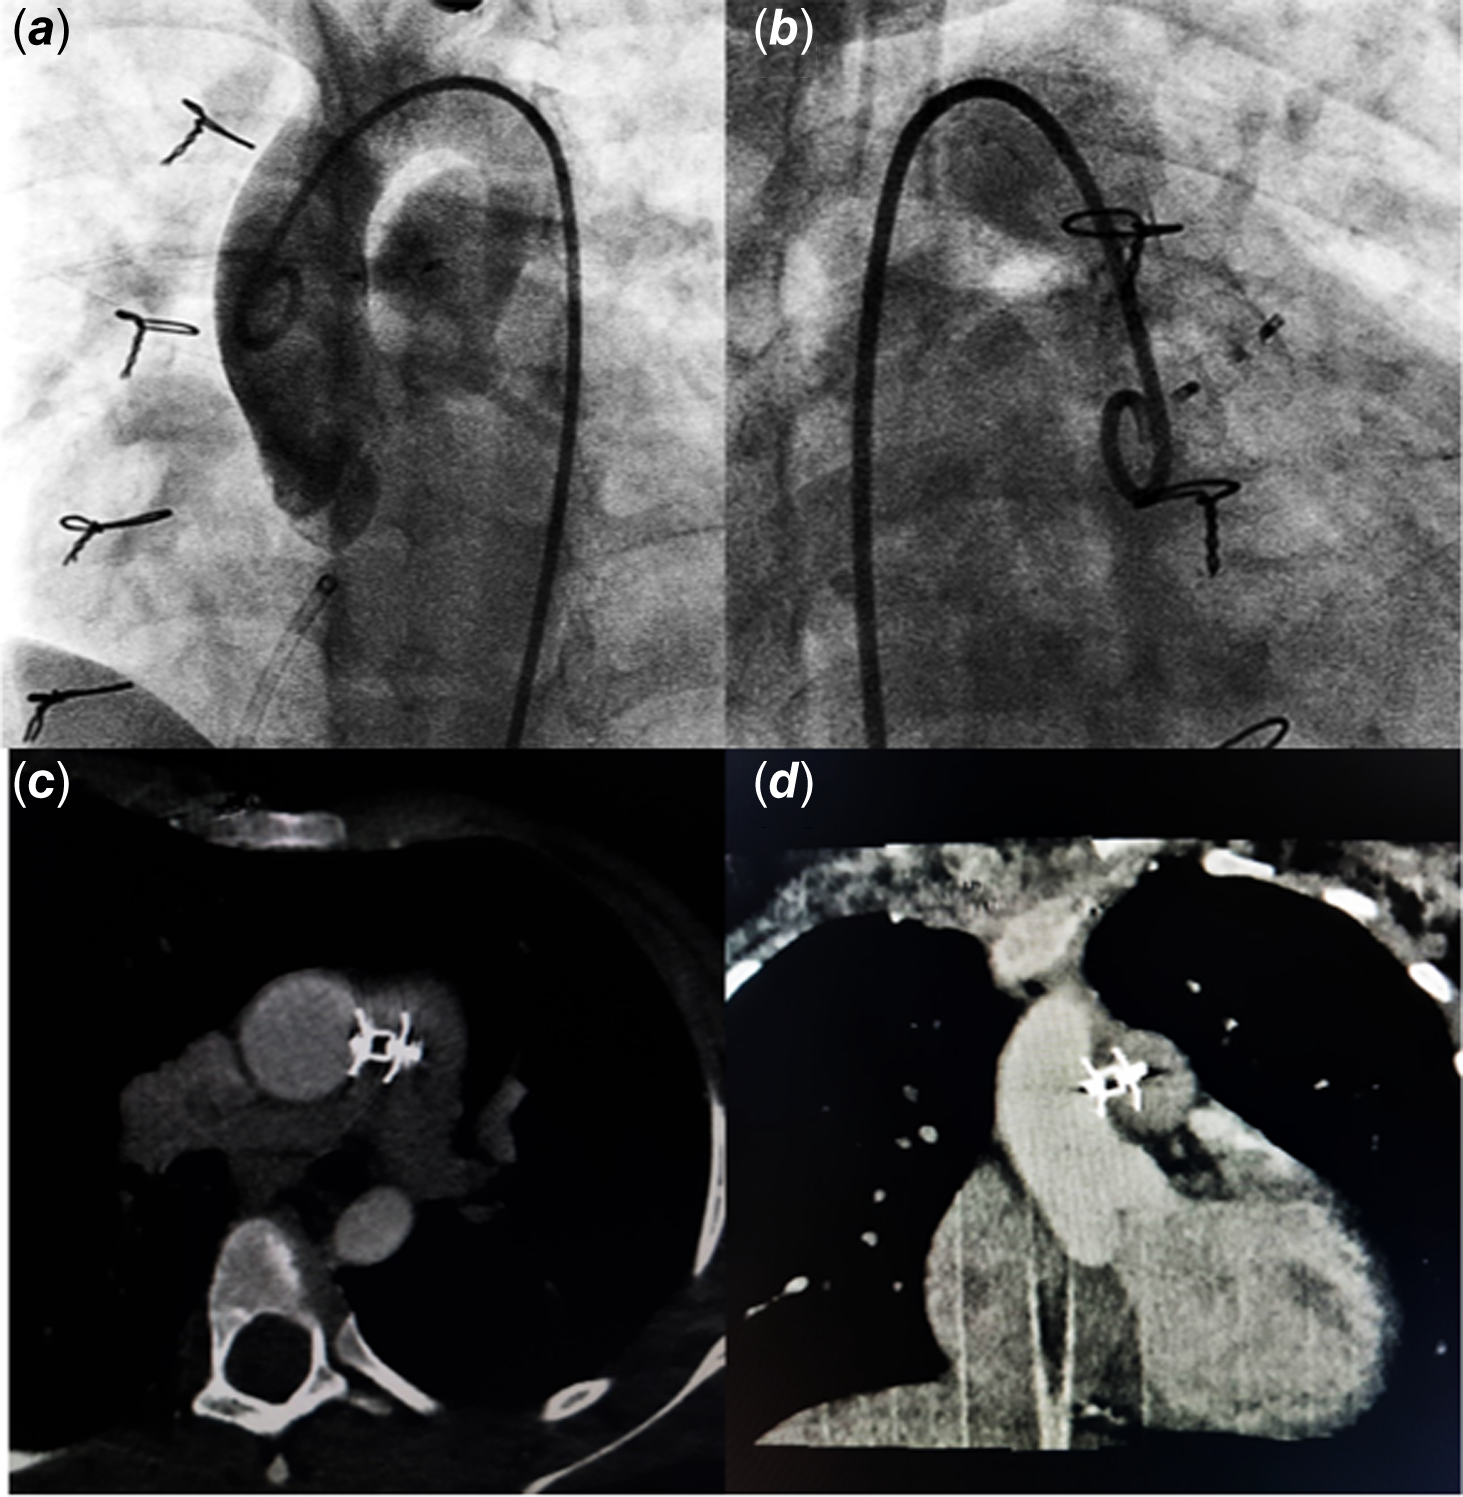

At 3-year follow-up, the defect was noted to have caused significant left ventricular volume overload with preserved ventricular functions. The defect measured 3–4 mm on echocardiography. The patient was catheterized to delineate the defect, which measured 3.1 mm and 11 mm distal to aortic sinuses in Left Anterior Oblique (LAO)/cranial and Right Anterior Oblique (RAO)/cranial projections (Fig. 1). Haemodynamic assessment showed pulmonary blood flow (Qp):Systemic blood flow (Qs) ratio 2.4:1 with normal pulmonary artery pressures (mean pulmonary artery pressure 18 mmHg). Aortopulmonary window was crossed using a JR4 catheter and a 0.035 exchange length glide wire through aortic end and engaged in distal left pulmonary artery. A 10 mm snare catheter used to snare the wire and railroad was established through right femoral artery. A 7×5 Konar-MF occluder (Lifetech, China) was selected to close the defect. It has a soft woven mesh with a flexible waist primarily designed for perimembranous Ventricular Septal Defect (VSD) closure. It has a double-sided screw for retrograde and antegrade approach and can be delivered through a small delivery sheath. The delivery cable is also slim to avoid untoward damage. Keeping in view, the acute angulation on aortic end entry point, sheath was passed in antegrade fashion. High tensile end was released on aortic side and low tensile end on pulmonary end. The device was released successfully with no residual defect on aortogram (Fig. 2 a, b) or echocardiogram. The flow is seen through the device, which disappeared completely the next day. This relates to the fact that Konar-MF occluder devices up to 8×6 come without a membrane, hence a small delivery sheath (4F, 5F). Sizes 9×7 upwards have a membrane inside the device and would require a relatively large sheath (6F, 7F). The patient was discharged 24 hours after the procedure on aspirin 5 mg/kg daily to be continued for 6 months. Short-term follow-up with repeat transthoracic echocardiogram and cardiac CT at 9 months should demonstrate excellent device profile with no residual leak, no branch pulmonary artery turbulence, and no aortic obstruction (Fig. 2 c, d).

Figure 2. a , b. Post-procedure angiogram. c , d. Follow-up CT angiography.